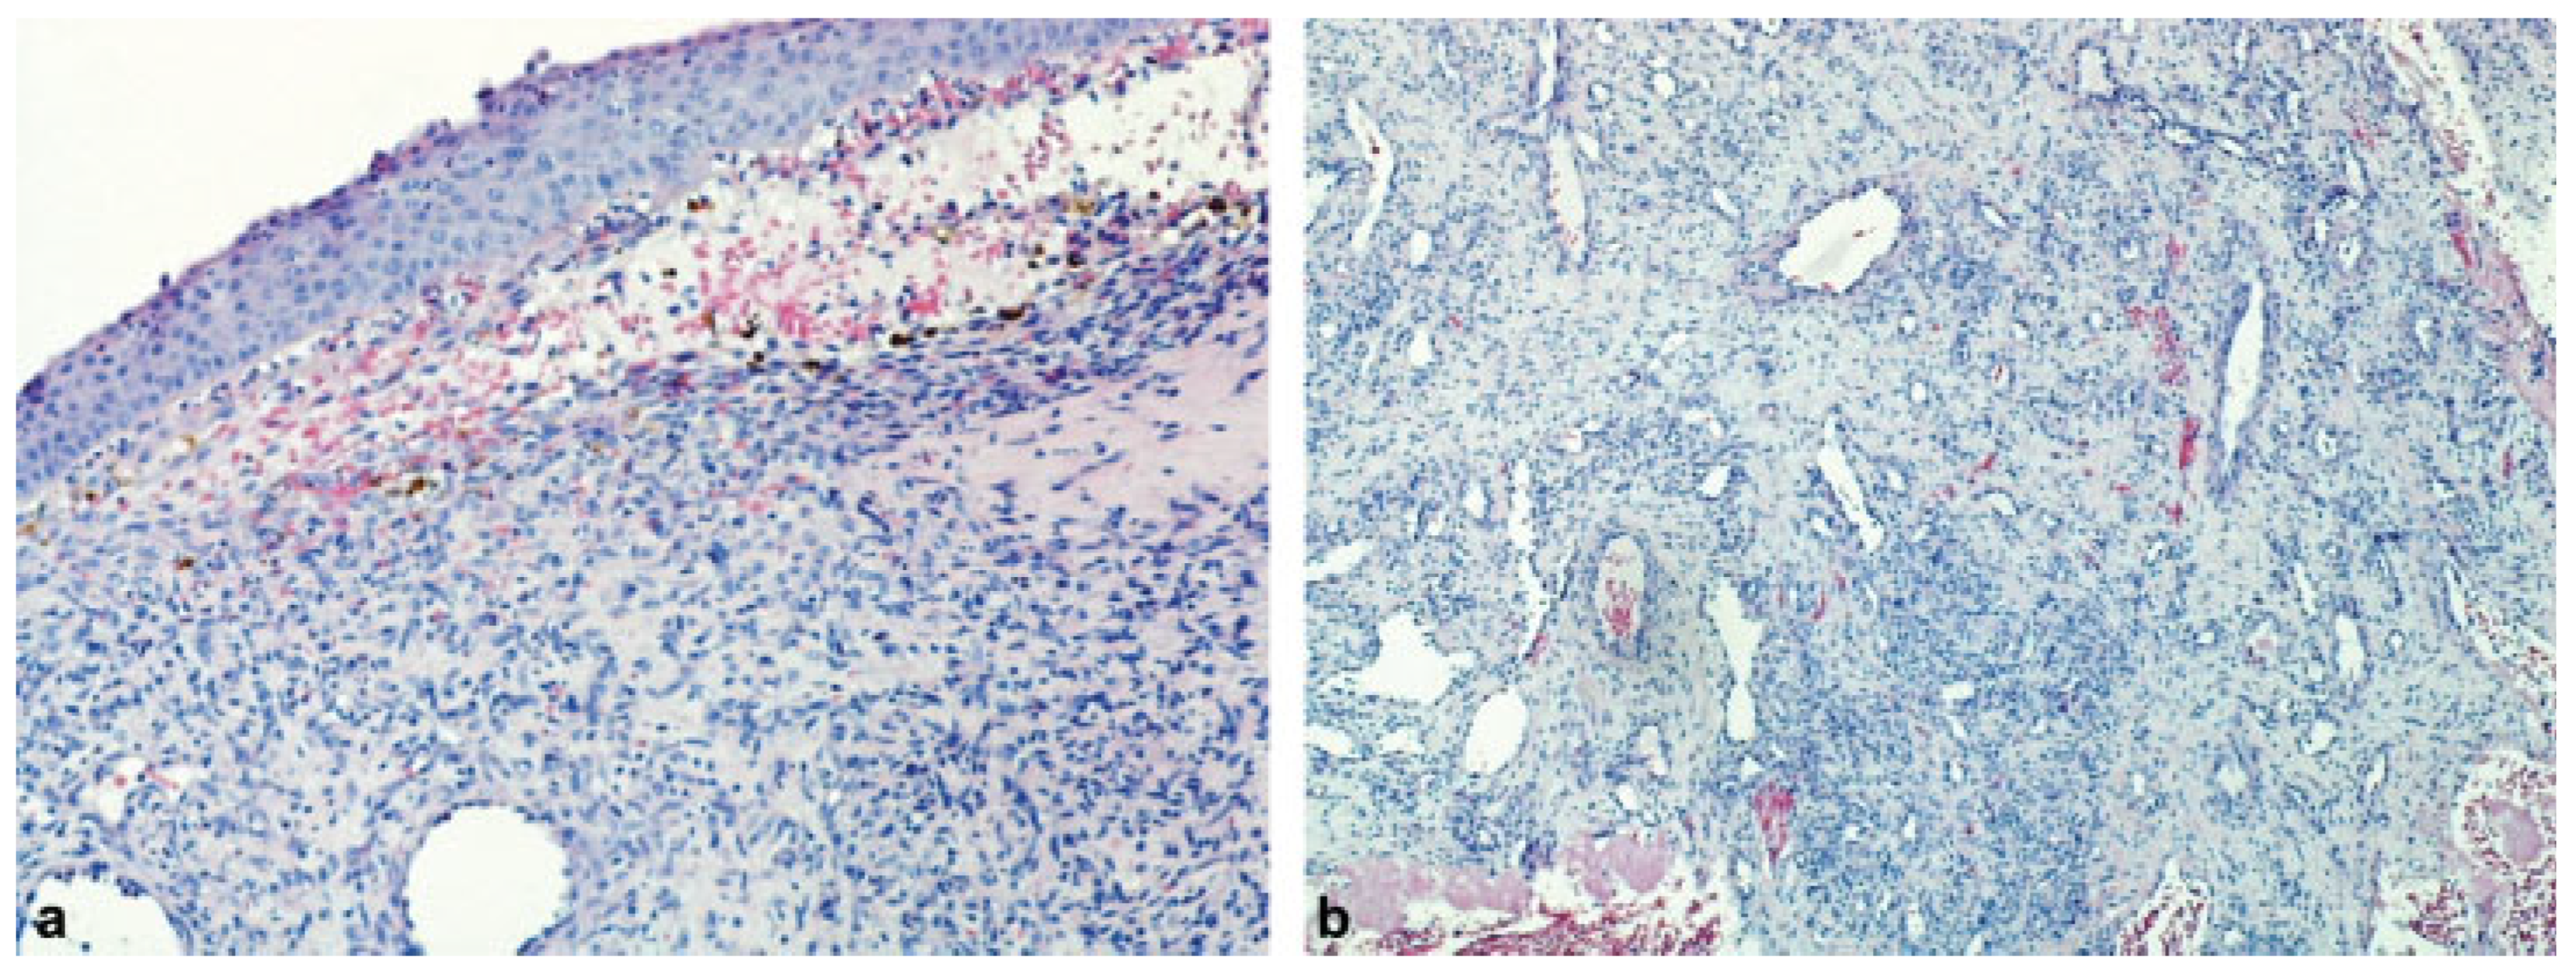

Extranasopharyngeal Angiofibroma Arising from the Anterior Nasal Septum in a 35-Year-Old Woman

Case Report

Discussion